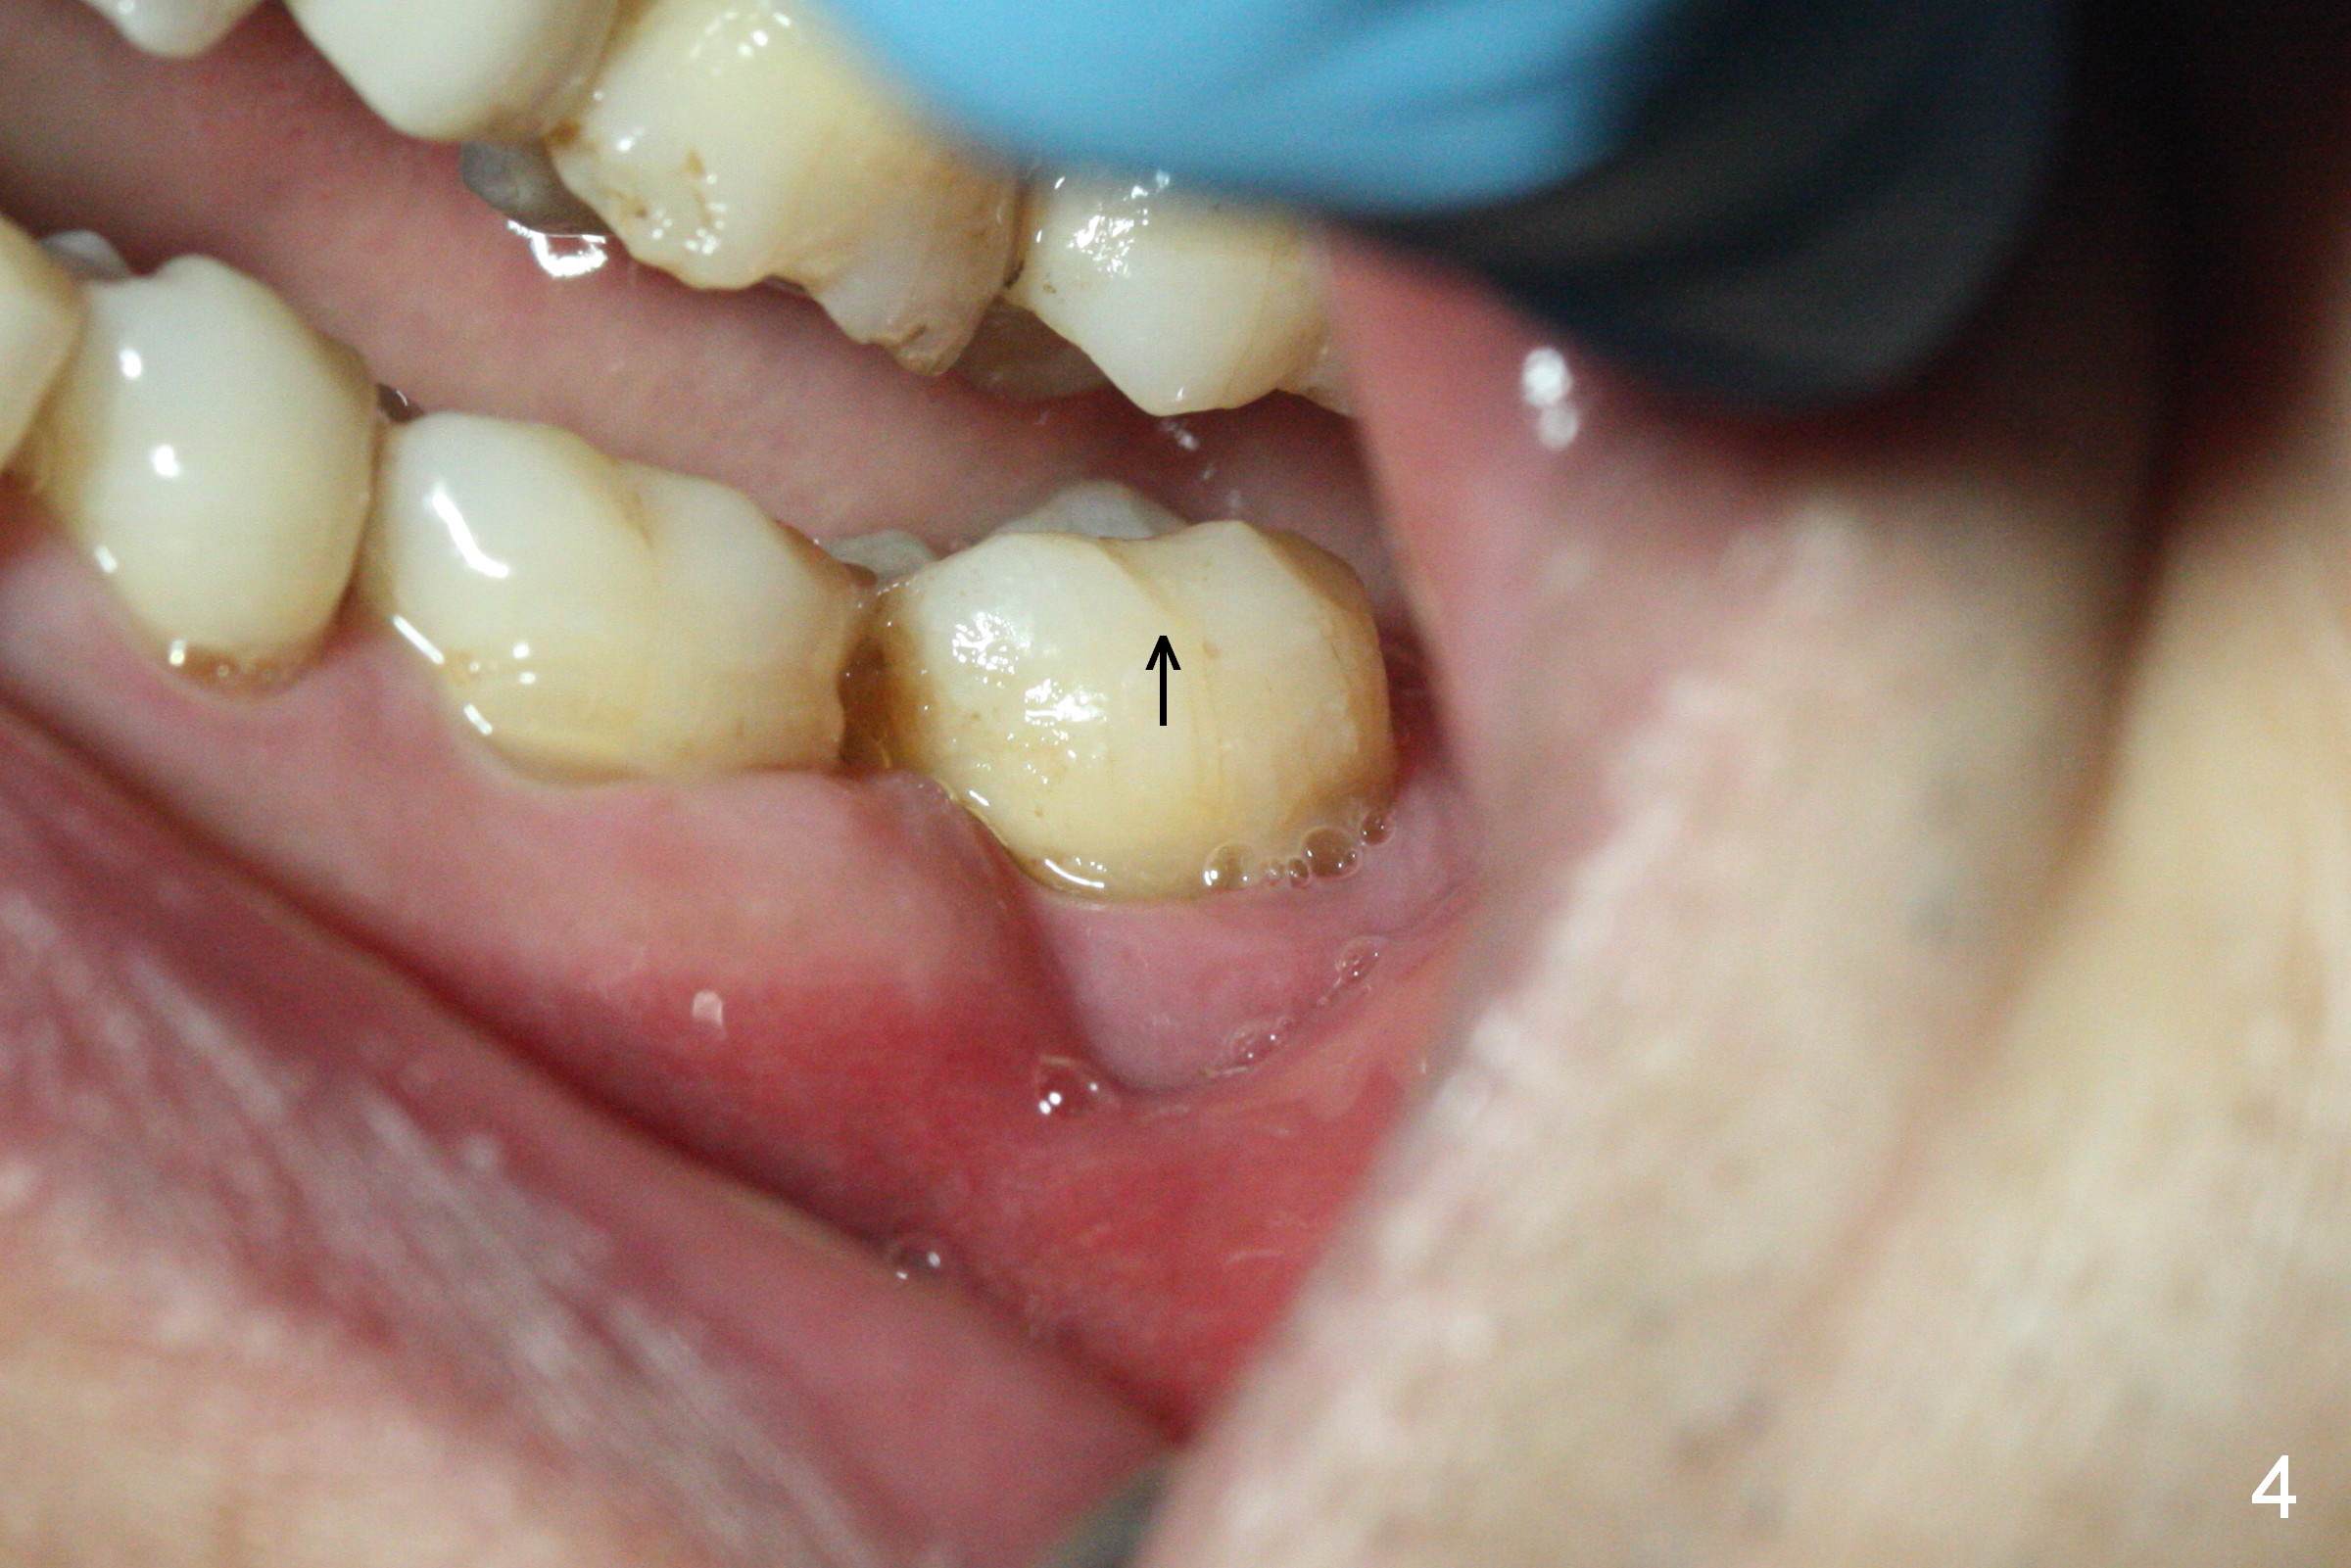

A 59-year-old man has history of chronic periodontitis (Fig.1 (taken in 2005), 2 (2014), 3 (2016)) involving the tooth #18. The bone loss may be complicated by bruxism. Large crown vs. narrow roots contributes to severe bone loss. An implant should be as long as possible and placed as coronally as possible to tackle crown/implant ratio issue. To prevent peri-implantitis, the implant may have to be placed deep. It appears that the bone height is more favorable mesially than distally (Fig.3). After extraction of the supraerupted and loose tooth (Fig.4; no Antibiotic), explore the socket to determine the favorite osteotomy site, most likely the mesial socket, lingually.